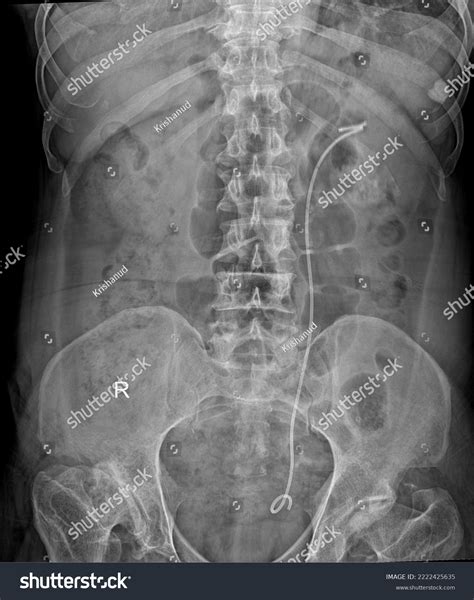

A Kub Abdominal X Ray, also known as a KUB (Kidneys, Ureters, Bladder) X-ray, is a type of abdominal radiograph that provides a detailed view of the abdominal cavity. This imaging technique is commonly used to assess the organs and structures within the abdomen, including the kidneys, ureters, bladder, intestines, and other soft tissues. The primary goal of a Kub Abdominal X Ray is to detect abnormalities such as obstructions, infections, or tumors.

• Presence of foreign objects or obstructions

A Kub Abdominal X Ray can reveal a wide range of findings, some of which are more common than others. Here are a few examples:

Finding Description

Bowel Obstruction Blockage in the intestines, often caused by adhesions, hernias, or tumors.